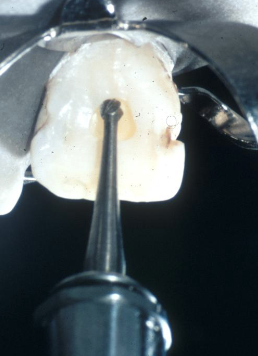

What bur is used for access opening?

701 in high-speed handpiece (may use slow speed when closer to chamber)

This bur is used to cut the cavo-surface outline

#701